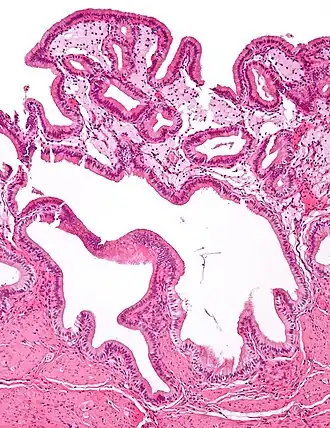

Micrograph of cholesterolosis of the gallbladder -